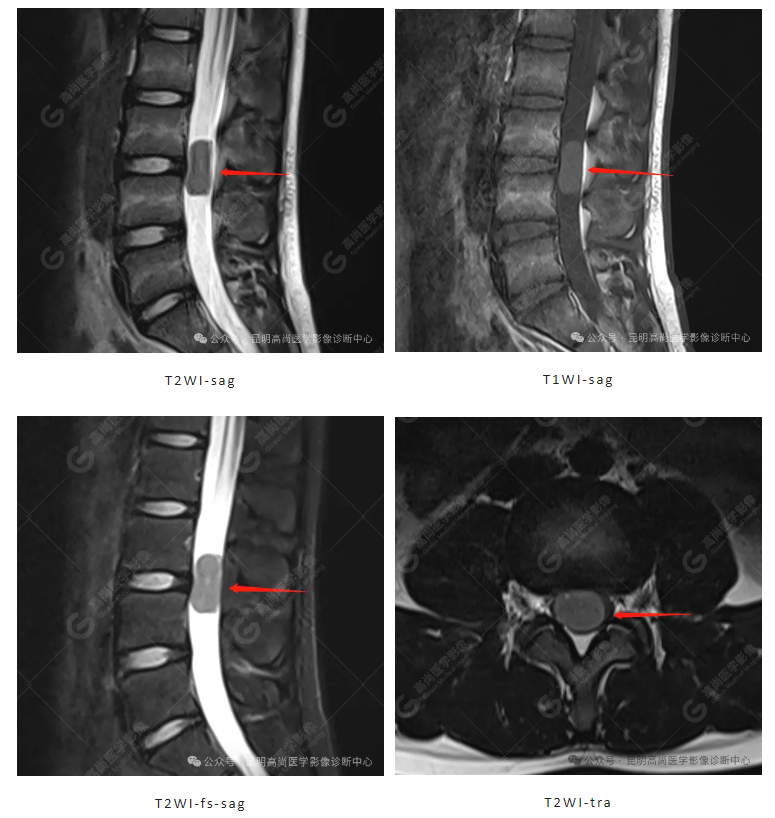

腰 3-4 椎体平面椎管内占位,考虑粘液乳头型室管膜瘤可能,神经源性肿瘤或其他待排。

影像学检查中 MR 对病灶显示较好,呈类圆形、哑铃型,边界清,多位于椎管后外侧,T1WI 呈略低信号,T2WI 呈高信号,中心可囊变、偶见出血,增强后肿块明显强化,伴出血时不均匀强化,肿块从椎管内穿过椎间孔向椎管外生长,呈哑铃型,相应层面椎间孔扩张。